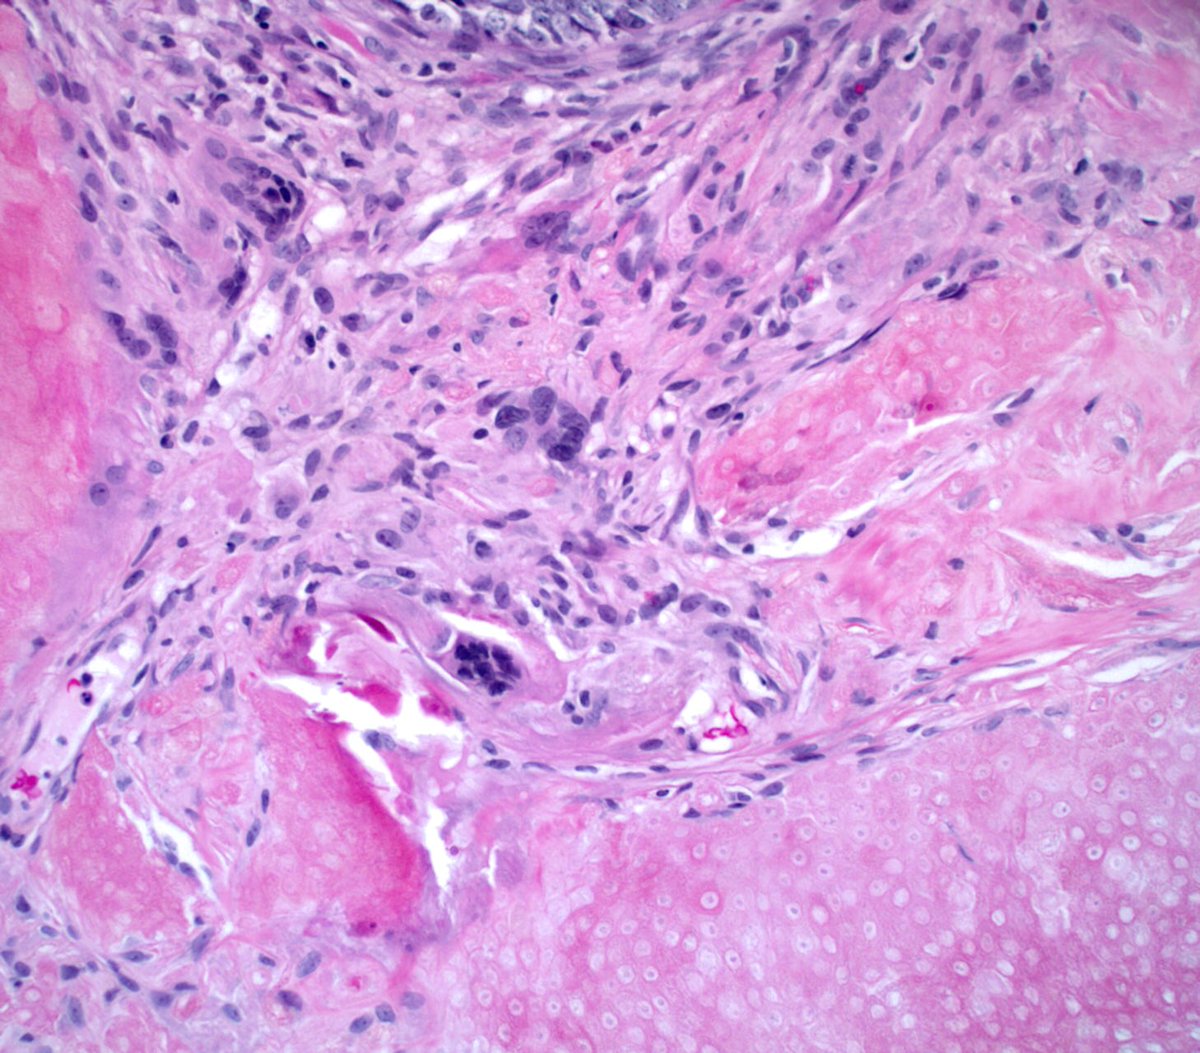

#Granulomatous#vasculitis possible case of granulomatosis with polyangitis aka#Wegener's dz#dermpathpic.twitter.com/a33cuMsQiH

-